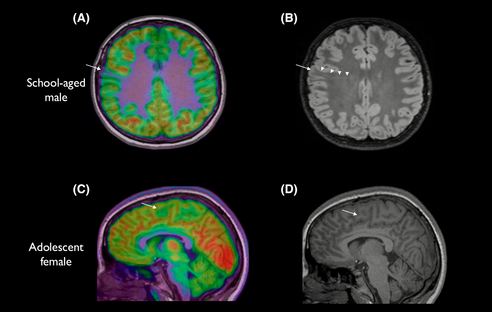

Pour ce faire, les chercheurs ont recruté 71 enfants et 23 adultes souffrant de crises d’épilepsie récurrentes dues à une dysplasie corticale. Des données d’IRM de surface et de tomographie par émission de positons (TEP) au FDG (un marqueur radioactif) ont été utilisées pour former le modèle d’IA. La TEP-FDG permettrait de mieux distinguer les tissus dysplasiques de ceux sains.

Les enfants étaient répartis en cohortes d’entraînement et de test, tandis que les données des adultes ont été utilisées pour valider les performances du détecteur. Parmi les participants, 80% n’avaient pas pu être diagnostiqués avec certitude avec leurs résultats IRM. En revanche, la cohorte de test (17 enfants) a été diagnostiquée avec un taux de réussite de 94% avec l’outil d’IA. Sur les 17 enfants du groupe test, 12 ont été opérés et 11 n’ont aujourd’hui plus de crises d’épilepsie.